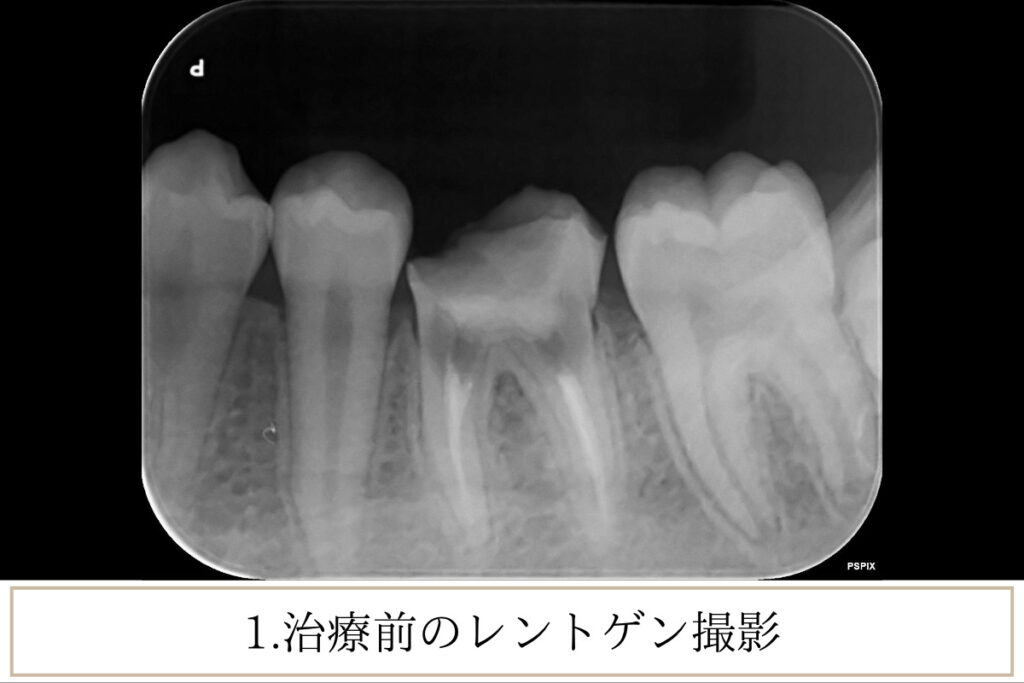

当院は、マイクロスコープや歯科用CTといった精密機器を活用し、診査・治療を行っています。疾患原因の特定や治療精度を高めるには、必須ともいえる機器です。事前の診査、検査、正しい診断をするためには、精密機器を駆使し、適切な治療を行っていくことが必要です。誤った診断をすれば、歯科の腕だけでは、適切な治療が行えるとはいえません。